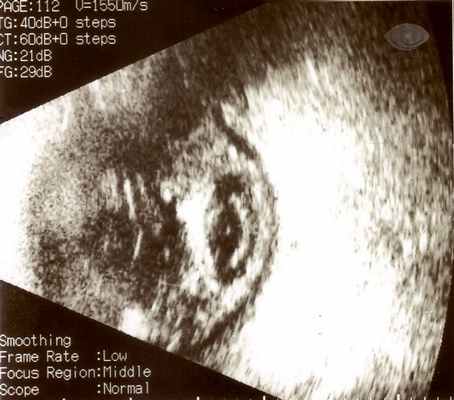

При дополнительном ультразвуковом исследовании глаза определяют отек оболочек и помутнения различной выраженности в стекловидном теле – признаки активного воспалительного процесса.